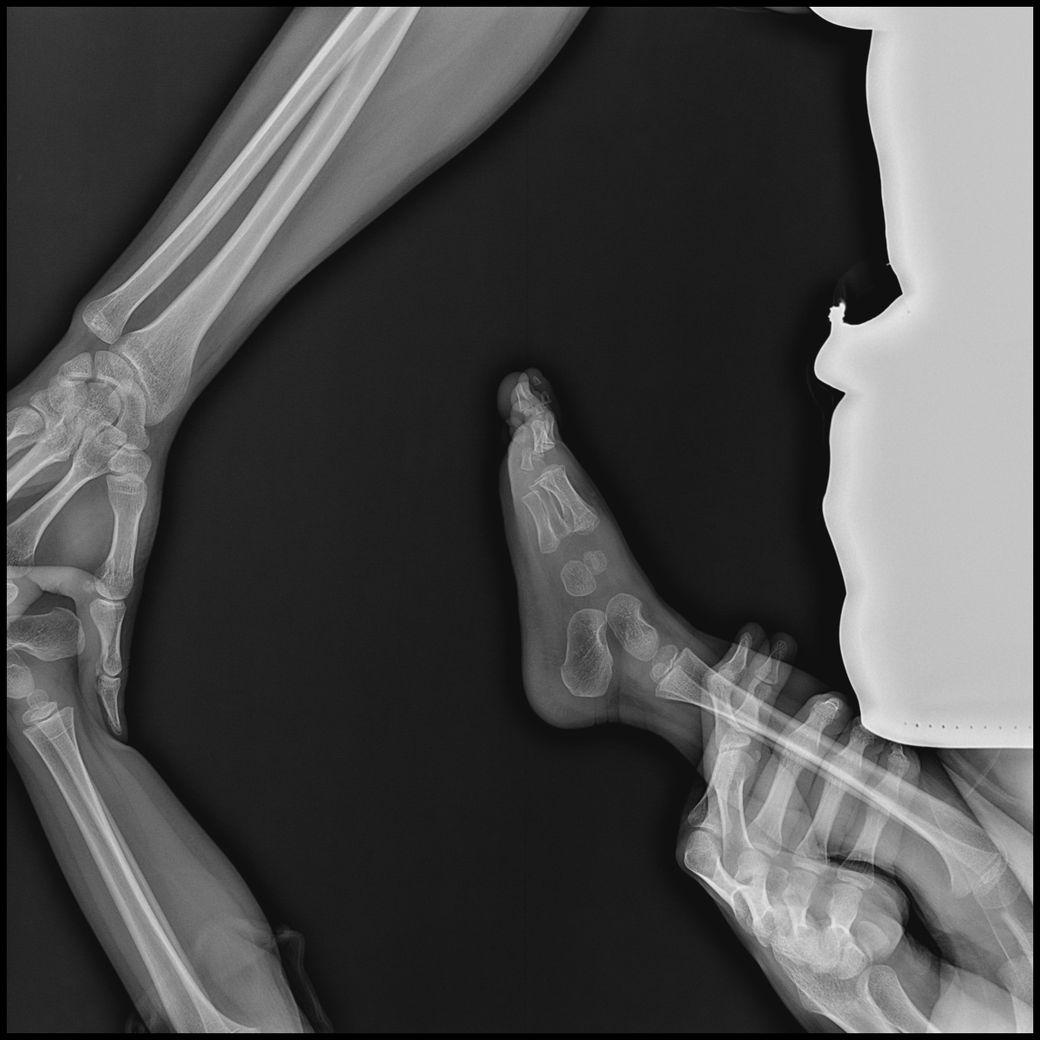

아기 손발 엑스레이를 찍게되었는데요.

손목, 발목까지 6-8장 찍기로 안내받았으나,

고관절,복부일부,생식기등 민감부위등이 추가로 촬영되었고

발도 다리가 다 찍혔고 총 19장이 찍혔습니다.

- 몸통일부+손같이찍힘 : 6장

- 손부터 팔꿈치까지 : 3장

- 발~다리사진 : 10장